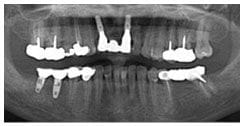

X 光片

術前X光片

術後X光片